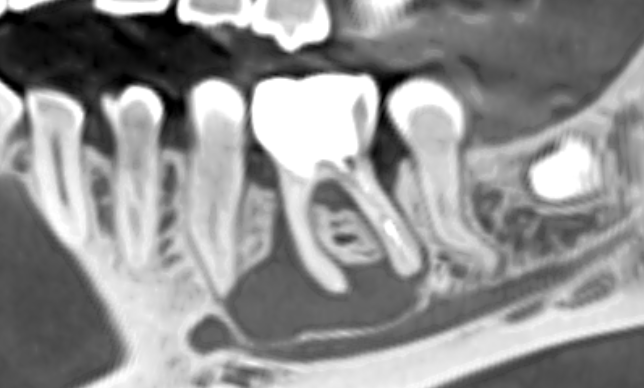

Воспалительный процесс. Если возле зуба сформировался очаг с воспалением (гранулема или киста), к тому же с выделением гноя, то операцию лучше отложить. А вот зуб удалить немедленно, иначе воспаление будет с каждым днем разрушать кость.

Недостаток костной ткани. Часто является следствием воспалительного процесса. Наращивание костной ткани в области лунки только что удаленного зуба, совмещенное с имплантацией – это всегда риск. Главная проблема заключается в том, что мягких тканей (десны) недостаточно для закрытия имплантата, так как лунка еще не зажила.